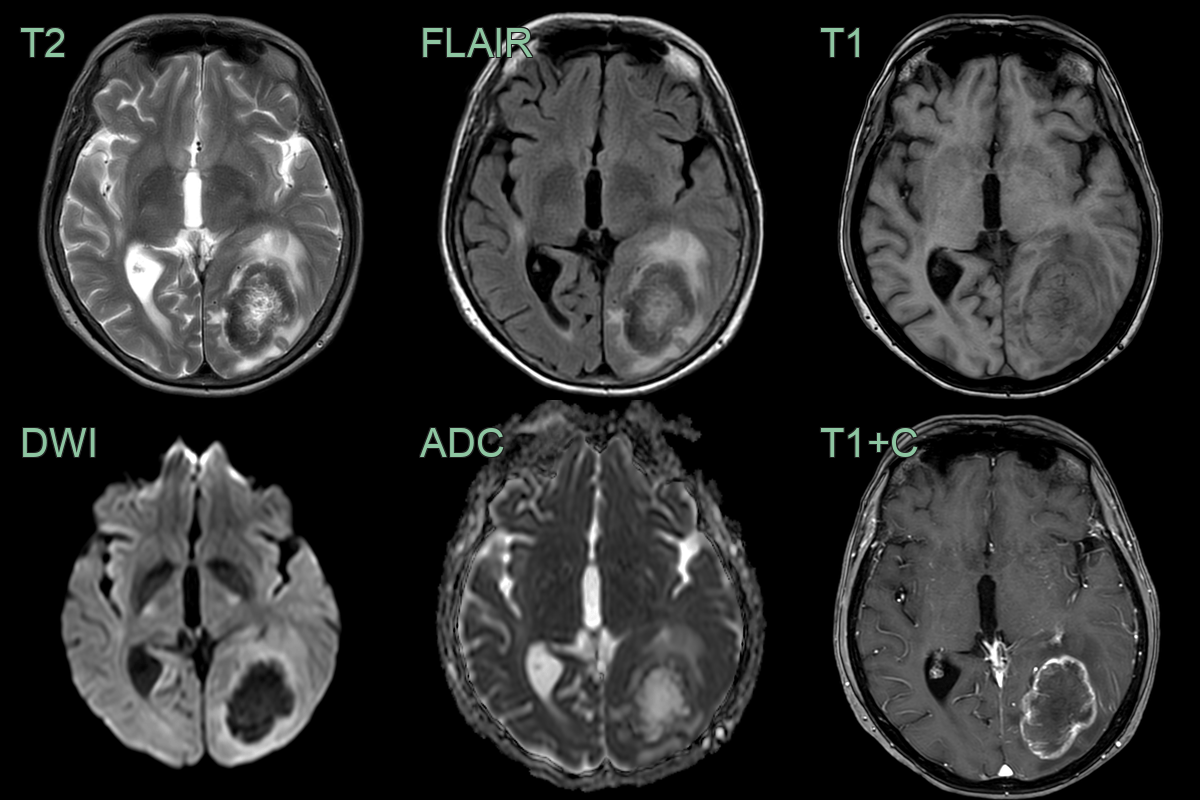

- A 70-year-old patient with small cell lung cancer presented with right leg weakness.

- MRI showed many peripherally enhancing lesions, the larges of which was in the left paracentral lobule.

- Following chemotherapy, MRI showed a marked reduction in the size of all of the lesions and the surrounding edema.